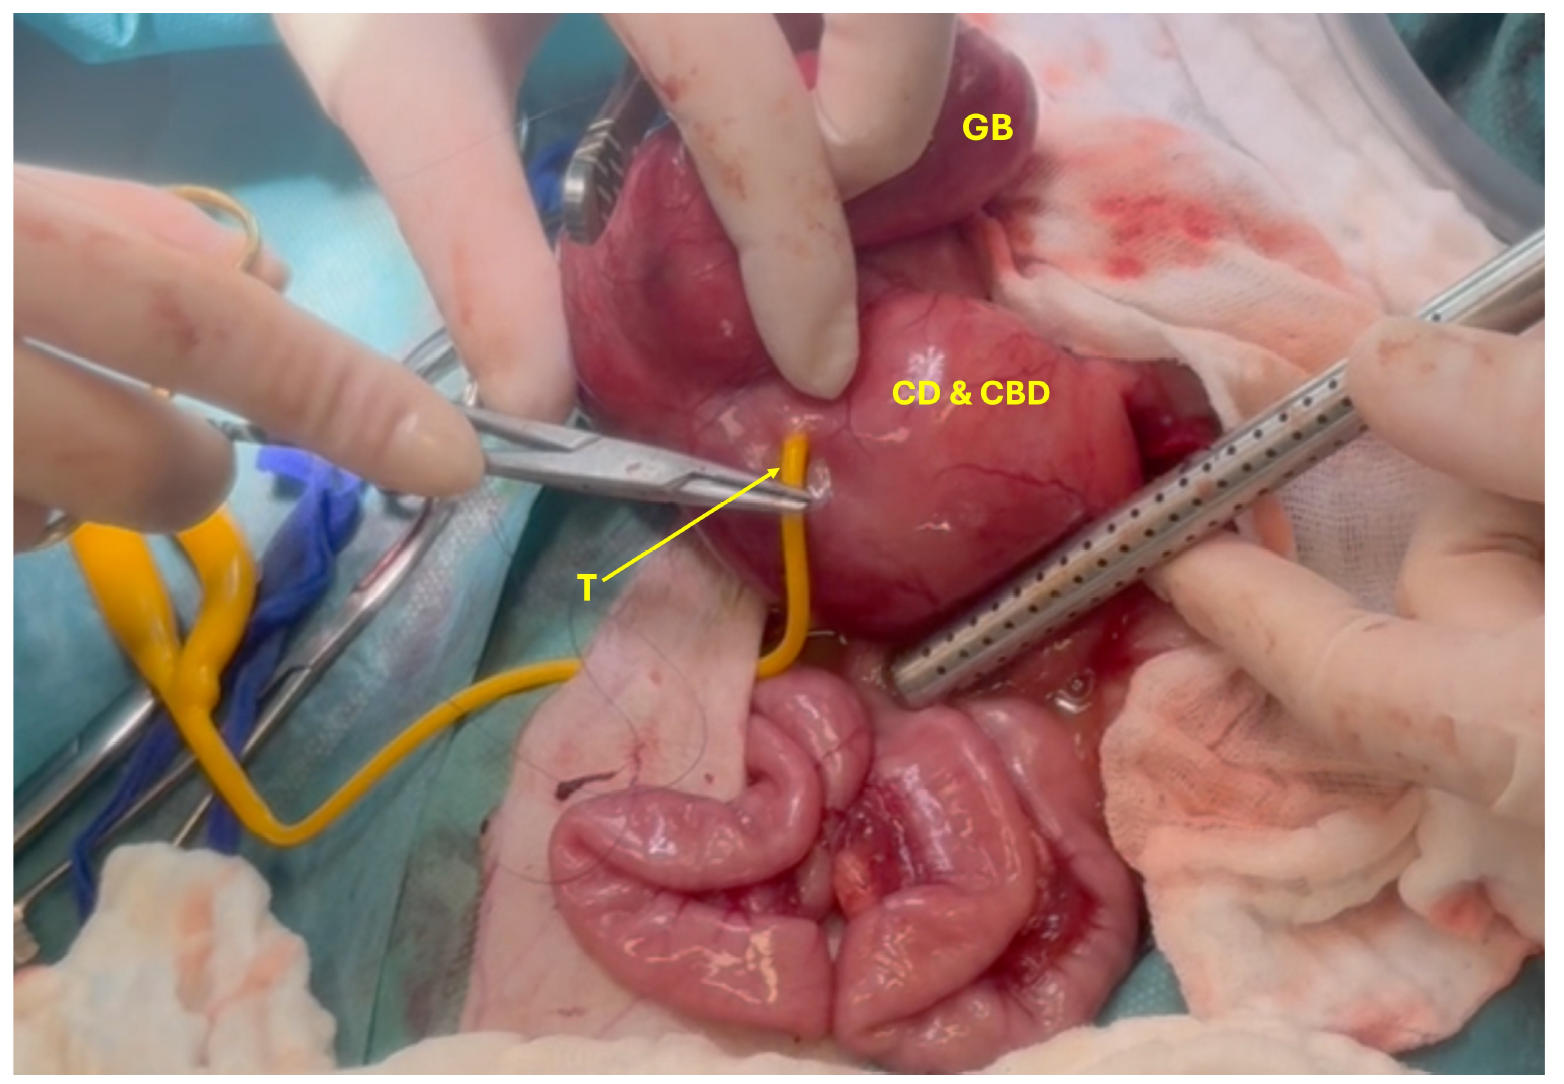

在完成腹腔检查后,从肝脏、增大的肠系膜淋巴结、十二指肠和胰腺右侧采集了活检样本和细菌学样本。仔细将胆囊从其窝中分离出来,并在胆总管内插入一根导管,以引流其内容物。导管留在原位,作为胆道造口管,以实现胆道引流并支持组织愈合(下图)。

↑ 将胆道造口管(T)放置在胆管(CD)和胆总管(CBD)中,以排空胆囊管、胆总管和胆囊(GB)。